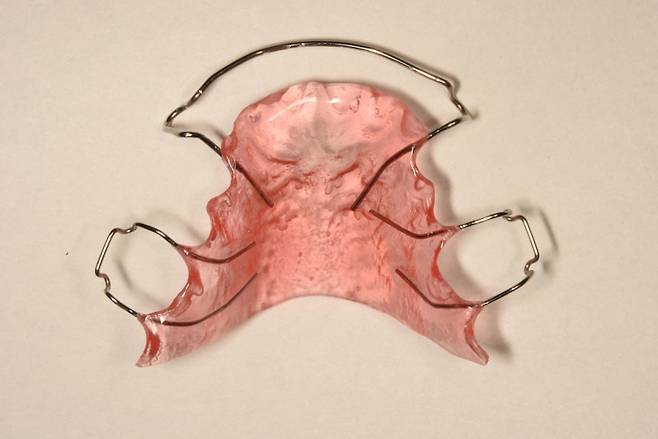

가철식 유지장치는 고정식과 달리 환자가 원할 때 언제든 붙이고 뗄 수 있는 장치다. 교정 치료가 끝난 후 보통 3개월은 식사·양치할 때를 제외하고 자는 시간까지 포함해 거의 온종일 사용해야 한다. 이후 환자 상태에 따라 잠잘 때 착용하는 등 사용 시간을 줄일 수도 있다.

가철식 유지장치를 착용한 채로 식사하면 장치가 망가질 우려가 있어 장치를 빼두는 게 좋다. 그러나 외식할 때 남들의 시선이 부담스러워 빼놓은 장치를 휴지로 감싸둔 채 식사하다가 깜빡하고 두고 가, 장치를 잃어버리는 경우가 종종 있다. 따라서 장치에 불필요한 외력이 가해지는 것을 막고, 분실도 방지하기 위해 장치를 사용하지 않는 동안에는 전용 통에 넣어 보관하는 게 좋다.

가철식 유지장치의 세척에 대해 안정섭 교수는 "장치를 적절히 세척하지 않을 경우 가철식 유지장치에도 치석이 붙을 수 있어, 칫솔을 이용해 장치를 주기적으로 닦아주는 것을 권장한다"라며, "치약을 사용해 장치를 닦으면 장치 표면이 마모되기 때문에 양치질하고 칫솔에서 치약을 헹궈 낸 뒤 가철식 유지장치를 닦아줄 것을 추천한다"라고 설명했다.

장치를 소독하기 위해 뜨거운 물에 삶아도 될까. 안 교수는 "삶으면 장치의 플라스틱 부분이 변형해 장치를 사용할 수 없게 된다"며 "시중에 교정용 유지장치 소독을 위한 세정제가 판매되는데, 장치 디자인에 따라 특정 세정제를 사용하면 장치의 철사 용접 부분이 망가지는 경우도 있어 사용 전 치과의사에게 문의하는 게 안전하다"고 답변했다.